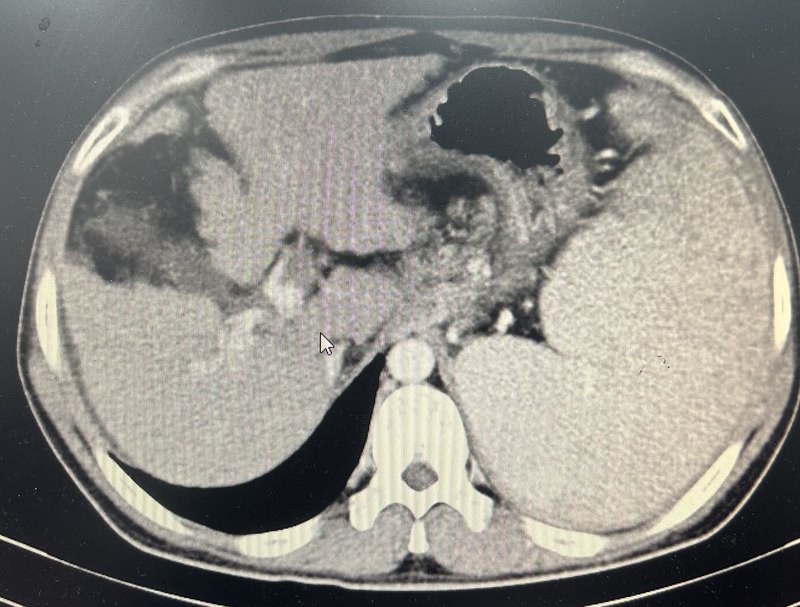

患者中年男性,因?yàn)楦雇锤姑?天,加重1天到我院急診科求診,急診超聲及ct提示門脈左右支主干、脾靜脈及腸系膜上靜脈血栓形成。門脈左支血栓形成。門脈右支血栓形成。門脈主干及脾靜脈血栓形成。腸系膜上靜脈血栓形成??鼓惶旌蟾雇窗Y狀稍有緩解,2023.9.26行經(jīng)腸系膜上動(dòng)脈置管溶栓治療,尿激酶25萬U,q6h,2023.10.1拔管,繼續(xù)經(jīng)靜脈溶栓治療,尿激酶25萬U,q8h,患者肝素過敏,溶栓期間利伐沙班15mg,bid。10月7復(fù)查ct,門脈脾靜脈及腸系膜上靜脈血栓變化不明顯,但是患者腹痛腹脹癥狀基本消失,可正常進(jìn)食及排便,給予出院繼續(xù)口服利伐沙班抗凝治療。2023.11.14患者復(fù)查ct,提示門靜脈、脾靜脈及腸系膜上靜脈血栓大部分消失,門脈主干仍然殘存少許血栓。門脈左支血栓基本消失。門脈右支血栓基本消失。腸系膜上靜脈血栓基本消失。脾靜脈血栓基本消失。門脈主干似有少許血栓殘余。繼續(xù)密切觀察,繼續(xù)抗凝治療,利伐沙班20毫克,qd。點(diǎn)評(píng):門脈血栓臨床多見,治療方案選擇也存在一定的爭議,我們既往采取抗凝治療聯(lián)合經(jīng)腸系膜上動(dòng)脈置管溶栓治療不同程度門脈血栓患者均取得良好效果。此患者就診時(shí)候血栓負(fù)荷極大且腹脹腹痛癥狀明顯,隨時(shí)有腸壞死風(fēng)險(xiǎn),采取腸系膜上動(dòng)脈置管溶栓加抗凝的方案是否可以取得良好療效術(shù)前其實(shí)我們并沒有很大的把握。我們和患者充分溝通各種治療方案后,患者愿意選擇先嘗試這個(gè)治療方案,但是治療12天后雖然患者癥狀基本消失,但是復(fù)查增強(qiáng)ct,血栓變化并不明顯,這個(gè)時(shí)候如何選擇下一步治療方案,也會(huì)存在較大的分歧,我們和患者充分溝通后采取耐心抗凝的方案,一個(gè)月后復(fù)查提示血栓基本消失,這個(gè)案例或許提示即使在血栓負(fù)荷很重的患者采取這個(gè)方案依然可能取得滿意的療效,值得更多嘗試。對(duì)于門脈血栓負(fù)荷較重的患者,介入同道曾嘗試經(jīng)皮經(jīng)肝穿刺取栓及置管溶栓的方案,近年來也有不少同道采取直接tips通道抽栓及溶栓的方案,這兩個(gè)方案風(fēng)險(xiǎn)費(fèi)用均遠(yuǎn)高于經(jīng)腸系膜上動(dòng)脈置管溶栓,但是效果是否優(yōu)于經(jīng)腸系膜上動(dòng)脈置管溶栓仍然存在爭議。根據(jù)肝硬化門靜脈血栓管理專家共識(shí)(2020年,上海)引用一項(xiàng)隨機(jī)對(duì)照試驗(yàn)比較了經(jīng)腸系膜上動(dòng)脈持續(xù)泵入尿激酶(劑量為15000IU·kg?1·d?1)與TIPS治療肝硬化PVT的療效差異,雖然兩組間的門靜脈主干血栓的再通率相近,但溶栓組的腸系膜上靜脈及脾靜脈血栓的再通率顯著高于TIPS組,且肝性腦病發(fā)生率明顯更低。提示該共識(shí)意見似乎更傾向于推薦采取經(jīng)腸系膜上動(dòng)脈置管溶栓的方案。